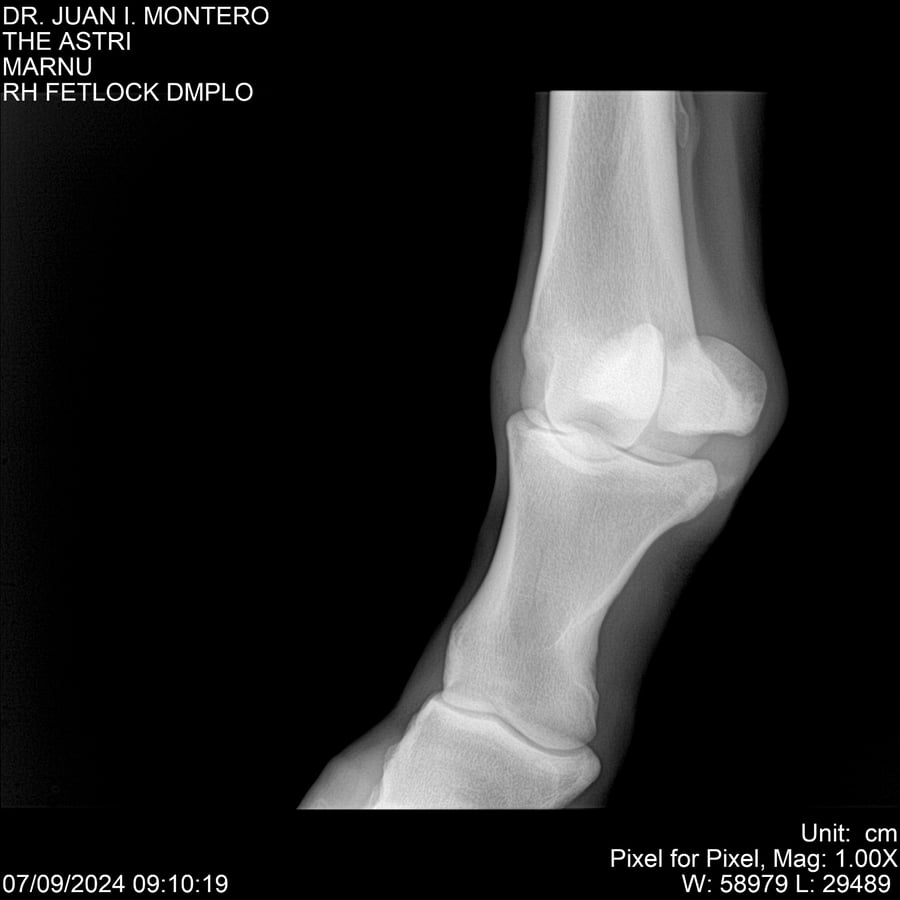

LOTE 10, THE ASTRI Lote Anterior Volver al remate Lote Siguiente Ficha Contacto Montevideo - Ficha del Lote Identificador: #282514 Categoría: Yeguarizos Montevideo - 60 Visualizaciones ClicData Contacto Empresa: Abelenda N. R., Walter Hugo Nombre*: Teléfono* : E-mail* : Mensaje Enviar Registrese gratis Este contenido Exclusivo está disponible sólo para usuarios registrados Ingresar